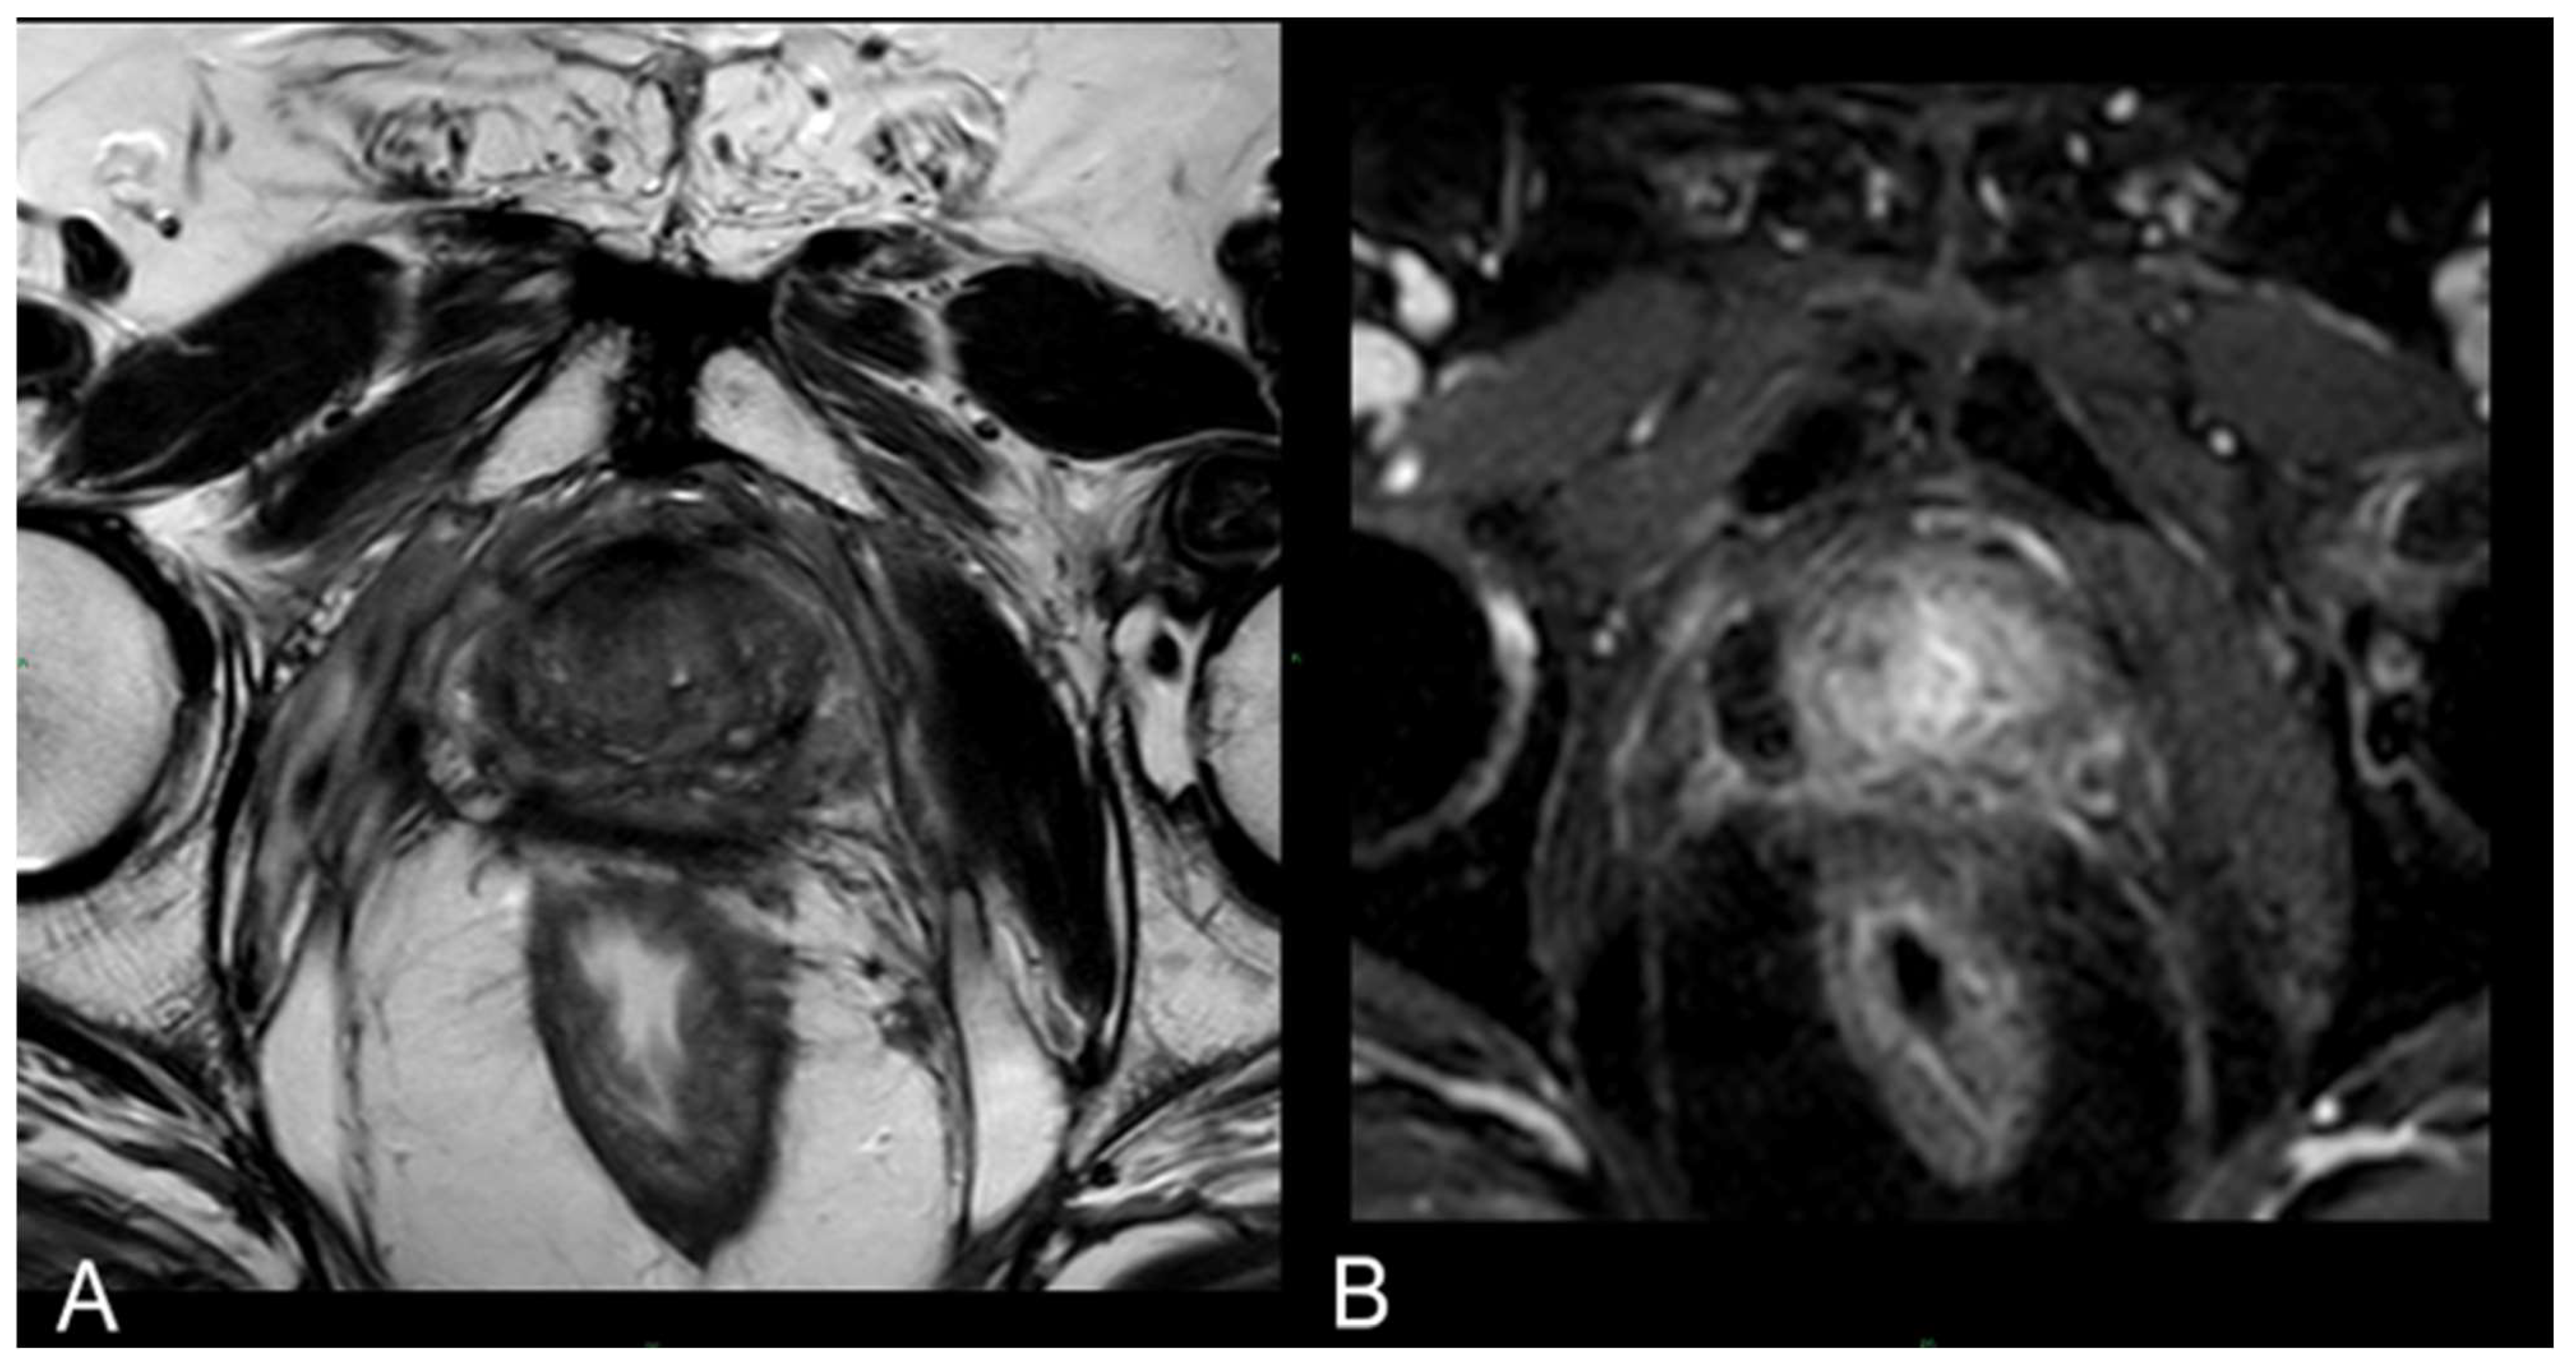

In 25% of the cases, the necrotic coagulation cavity was entirely reabsorbed and replaced by a fibrotic scar, as exemplified in Figure 5. Among the 25 patients, 20 did not exhibit any reliable focal contrast enhancement indicative of residual or recurrent neoplastic lesions within the treated area. This absence of neoplasia was subsequently confirmed by MRI/US fusion-guided target biopsies conducted at the 36-month follow-up.

Figure 5.

(A) T2-w axial sequence: small cavity filled with fluid. Some fibrotic tissue on the posterior edge of the right gland, with an external capsule retraction. Band-like right-side recto-prostatic angle hypointensity on T2-w imaging is the effect of mesorectum liponecrosis. (B) DCE T1-w Dixon sequence with fat suppression on axial plane: millimetric unenhanced cavity resembling a small cavity filled with proteinaceous fluid. Necrotic tissue is reabsorbed. Capsule retraction is visible.

Figure 6.

(A) T2-w sequence on axial plane: coagulation necrosis area (hypointense in T2W imaging) is smaller because of necrotic tissue reabsorption. (B) DCE T1-w Dixon sequence: The unenhanced devascularized area (hypointense in T1W + C imaging) is smaller in size compared with the 1st-month MR follow-up.

At 24 months–36 months: presence of a T2W hypointense scar tissue that almost completely replaced the original cavity (Figure 5).